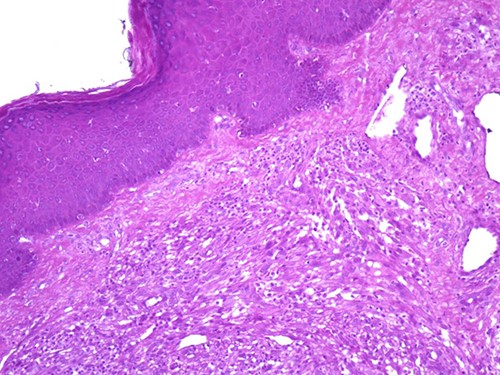

A 42-year-old man with no clinical history presented with a non-ulcerated polypoid skin nodule of the front side of the chest wall, which had grown over a period of 6 months, measuring 1,8 × 1,5 cm (Fig. 1). The lesion was removed completely with tumor-free margins of 0,5 cm. Microscopically, the tumor was composed of a diffuse infiltrate of polygonal cells with abundant granular cytoplasm and vesicular nuclei (Figs 2 and 3). There was no atypia or necrosis. The average mitotic count was one to two per 10 high-power field. Immunohistochemistry showed positive expression for CD10, CD68 and ALK with negative staining for CK AE1/AE3, CD34, S100 and HMB45 (Figs 4 and 5). No recurrence was noted during follow-up of 6 months.

The tumor is composed of epithelioid cells with abundant granular cytoplasm and vesicular nuclei (magnification at ×400).

Microscopically, DNNGCT are well circumscribed and composed of large spindled or polygonal to epithelioid cells with abundant granular cytoplasm [2, 4, 5]. The nuclei are vesicular with a single prominent nucleolus [7]. The mitotic index varies from 1 to 9 per 10 high-power field. A subset of this tumor show atypical cytologic features including nuclear pleomorphism and increased mitoses [1, 2, 4]. These histological features do not seem to correlate with a worse clinical behavior [1, 2, 4].